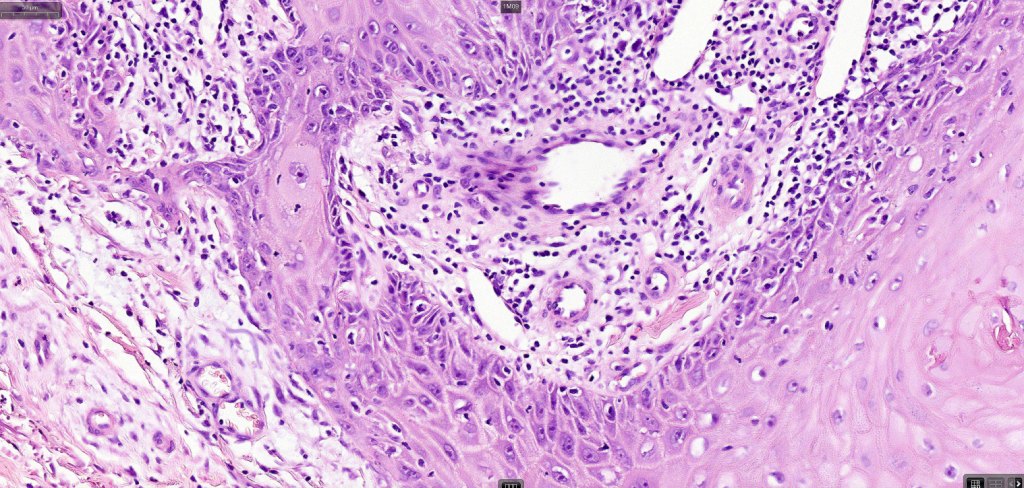

•Keratoacathoma (nowdays regarded as a variant of well differentiated squamous carcinoma) is characterized by a crateriform squamous epithelial lesion (dilated follicular infundibulum) with central keratin plug and adjacent collarette extending to the mid-dermis

•Well differentiated squamous epithelium often with a characteristic ground-glass appearance

•Neutrophil-rich microabscesses & necrosis

Below is a fascinating case shared on McKee Derm by Dr. James Simpson. There is an obvious keratoacanthoma but at the edge of the lesion there is marked atypia with nuclear enlargement and pleomorphism. This is also evident in the adjacent epidermis and in the deeper nests.